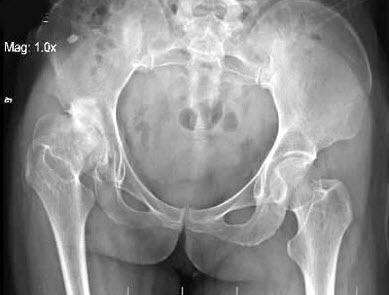

男,根据其正常骨盆影像图像,判断其最可能的年龄()

A.68岁左右

B.58岁左右

C.18岁左右

D.48岁左右

E.28岁左右